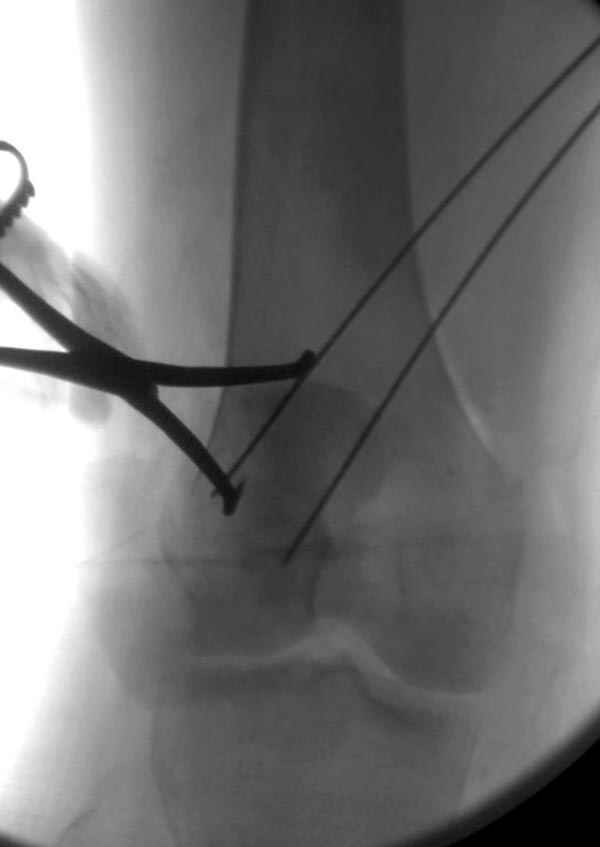

В приемное отделение поступает больная 22 лет, во время аварии ремень безопасности не был пристегнут, в крови большое количество кокаина.В приемном срочная интубация и седация, сделаны снимки.Диагностирован: открытый вывих левого коленного сустава.

Заключительный диагноз: Открытый вывих коленного сустава, перелом надколенника, разрыв собственной связки надколенника

На операции: Irrigation&Debridment около 10 литров раствора, по два стержня в сегменте, фиксация диагонального, с дефектом, перелома надколенника тремя cannulated 4мм шурупами, ушивание поперечного разрыва связки 5.0 Ethibon sutures, разрыв находился на 2 см ниже надколенника (срез чем-то острым), повторная ирригация раны, взятие посева на аэробическую и анэробическую культуру, окончательная фиксация стержней наружного фиксатора 50см Carbon Fiber Bars, вакуумное закрытие. Мониторинг показал, что компартмент синдрома нет.

Сегодня досылаю остальные снимки, которые не прошли вчера. Как вчера писал, после фиксации перелома надколенника с дефектом кости и собственной связки, наложили ваккуум и наружный фиксатор. (снимки 4-9)